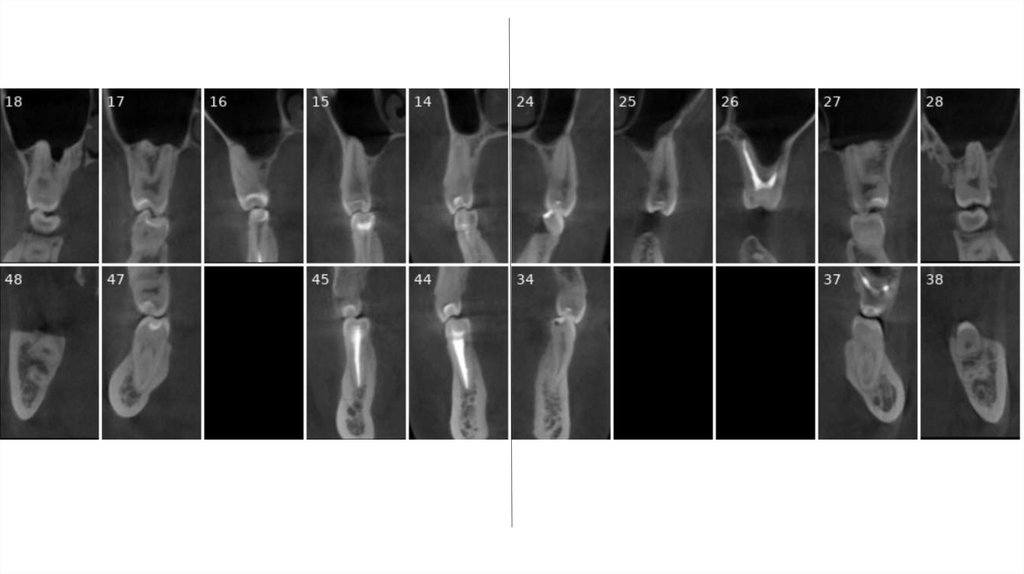

• Корни верхних моляров в пазухе (= невозможно двигать

зубы назад)

• Атрофия альвеолярного отростка на нижней челюсти

справа и слева

• Недостаточная толщина кости в зоне имплантации

нижних зубов

• Отсутствует костная ткань за верхними зубами мудрости

(=нет пространства для дистализации)